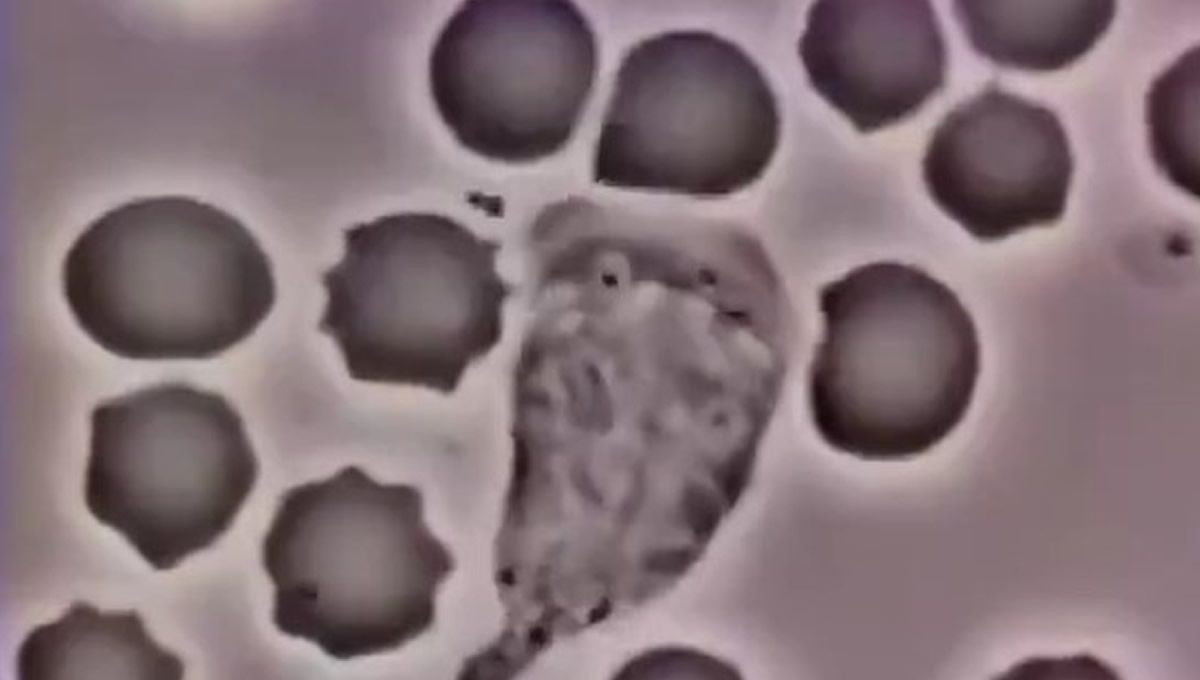

El sistema inmunológico protege al cuerpo de agentes externos, como pueden ser bacterias, virus, hongos o toxinas. Esto lo hace produciendo anticuerpos y células que atacan a los microorganismos. En este contexto, la cuenta de TwitterCerebro Digital (@digitalcerebro), enfocada a fomentar el conocimiento digital, ha publicado un vídeo en el que se observa cómo un glóbulo blanco humano persigue a una bacteria hasta atraparla y encapsularla. Gracias al vídeo, tomado a través de un microscopio, los usuarios de la red social pueden apreciar lo “fascinante del sistema inmunológico”.

El vídeo original fue capturado por David Rogers, ingeniero informático. Se tomó a través de un microscopio, y en él se puede observar cómo un glóbulo blanco, componente del sistema inmunológico humano, persigue a una bacteria hasta capturarla y encapsularla. Dicho vídeo, posteriormente, fue republicado por el farmacéutico español Gorka Orive.

El leucocito se encuentra en “plena persecución” de los microorganismos Staphylococcus aureus agregados a la película

En concreto, el metraje proviene de una película de 16mm que se filmó en la década de 1950 en la Universidad de Vanderbilt. En él se aprecia un leucocito polimorfonuclear humano (neutrófilo), en un extendido de sangre. Los leucocitos polimorfonucleares se producen a partir de la célula madre en la médula ósea, lugar en el que se almacenan y se liberan al torrente sanguíneo cuando el organismo los necesita. Estos viven en la sangre en torno a doce horas, y se diferencian de los glóbulos rojos porque poseen núcleo y son de mayor tamaño. Los leucocitos polimorfonucleares se dividen en neutrófilos, eosinófilos y basófilos.

En el vídeo, el glóbulo blanco se desplaza entre glóbulos rojos, que se identifican gracias a su color oscuro y a su forma redonda. Así, el leucocito se encuentra en “plena persecución” de los microorganismos Staphylococcus aureus agregados a la película. De este modo, el glóbulo blanco va persiguiendo al microbio, ignorando a los glóbulos rojos y las plaquetas. A su paso, va deformando y desplazando los glóbulos rojos que se encuentra.

Se cree que el quimioatrayente (sustancia química que atrae o repele las células) derivado del microbio podría ser el fragmento C5a del complemento. Esto se genera por la interacción de anticuerpos en la corriente sanguínea con la cascada de complemento o péptidos N-formilo bacterianos. Además, también se pueden ver plaquetas de sangre adheridas al vidrio subyacente.